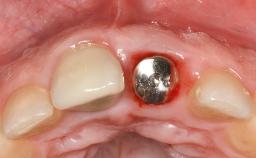

Maintenance of healthy peri-implant soft tissue as well as supporting peri-implant bone is an essential part of long-term success of implant therapy. An accurate maintenance protocol of peri-implant tissue health may prevent biological complications such as peri-implantitis. After the delivery of the prosthesis, patients should be followed up and clinical and radiological examinations should be performed on a regular basis to detect any etiological factors that may lead to such complications. This topic discusses properties of healthy and pathological conditions of peri-implant tissue, clinical and radiological examination methods of peri-implant tissue, as well as protocols for maintaining peri-implant tissue health.